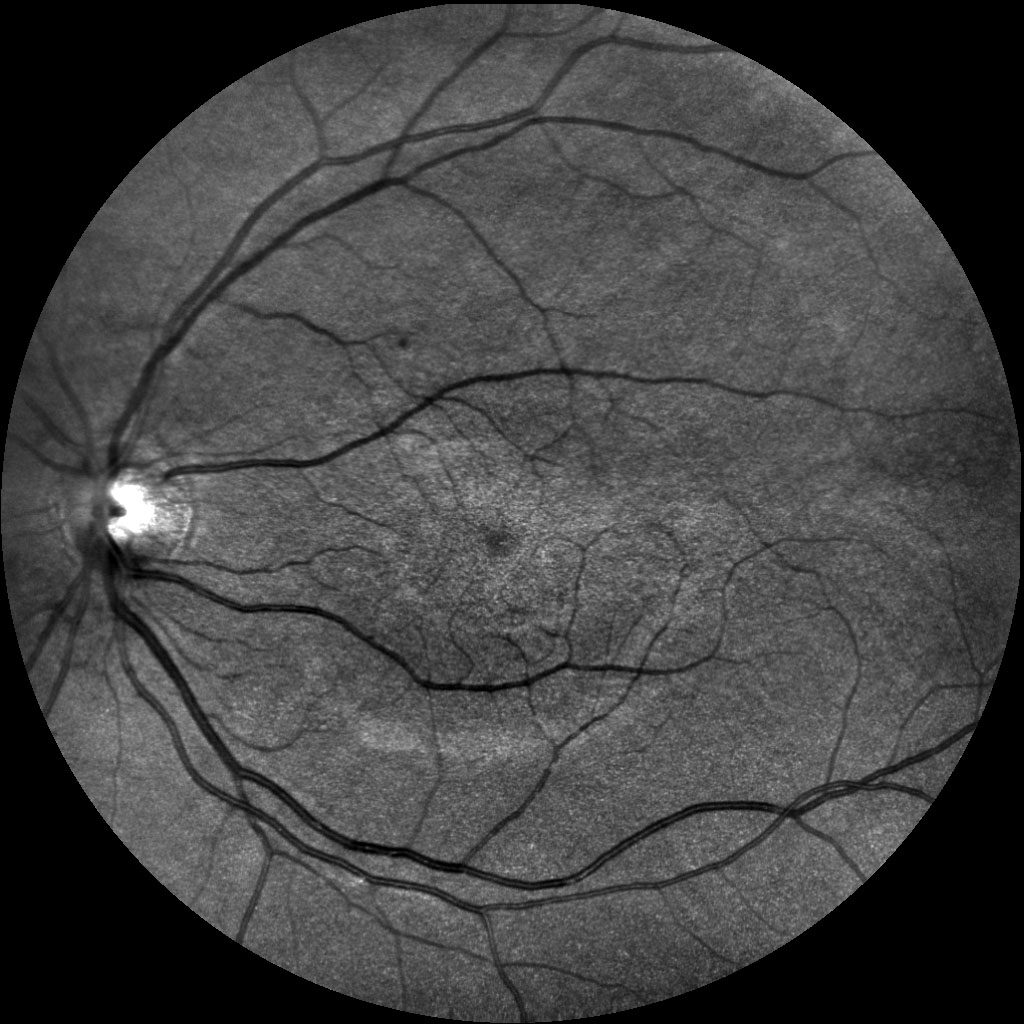

Dzięki technologi SLO – Scanning Laser Ophthalmoscope, podczerwieni oraz wiązki zielonego laseru, jesteśmy wstanie wykonać bardzo dokładny zrzut dna oka, dzięki czemu wykryjemy praktycznie każde zmiany w gałce ocznej. W realizacji takiego skanu nie potrzebne jest zakroplenie oka co znacznie usprawnia nam diagnostykę pod katem szybkości badania czy samopoczucia osoby poddanej tejże czynności. Badanie ma na celu wykrycie zmian w oku jak: jaskra, zaćma, zatory żylne, męty, retinopatie cukrzycową czy AMD(zwyrodnienie plamki żółtej), Pełna wizyta obejmuje: